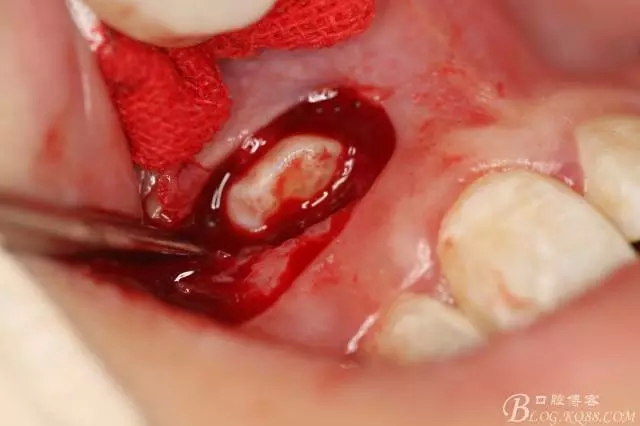

病例資料: 患者、柴xx、女、16歲。??茩z查及病歷如下圖: 患者同意我院正畸科建議,遂轉(zhuǎn)診倒外科。術(shù)前簽知情同意書。 治療過程: 圖1.術(shù)前的CBCT檢查:13阻生,疑為含牙囊腫??v剖面顯示12牙根吸收至根尖1/3。 圖2.局部麻醉下 。行唇側(cè)弧形切口,12松動(dòng)不到1°。 圖3.翻瓣、暴露骨面。 圖4.去骨、 暴露13牙冠 圖5.去骨、逐漸顯露13。 圖7.拔除13. 圖8.摘除囊壁 圖9.必須完整剝離囊壁。 圖10.摘除囊壁后形成的骨腔 圖11.超聲骨刀12根尖倒預(yù)備 圖13. 消毒棉球骨腔內(nèi)隔濕血液,紙尖干燥倒預(yù)備好的根管 圖14. 紙尖無血即可 圖15。MTA倒充填 圖16.骨腔填塞膠原蛋白海綿 圖17.拔除的13及摘除的囊壁 圖18.縫合 圖19.術(shù)后x線根尖片影像:MTA封閉根尖